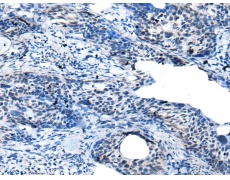

IHC positive control: |

Human cervical cancer |